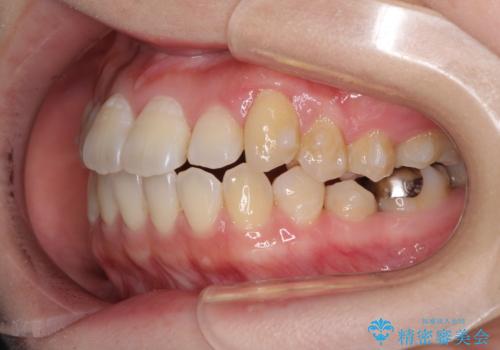

- 前歯がデコボコした上に口元が閉じにくいことを気にして来院された患者様です。

IPR(歯と歯の間を削る)と側方拡大では口の閉じにくさは改善できそうになく、一方で抜歯矯正を行うほどの突出感は認められませんでした。

親知らずを全て抜去し、歯列全体を後方に移動させることで口元の閉じにくさいを改善していくこととしました。